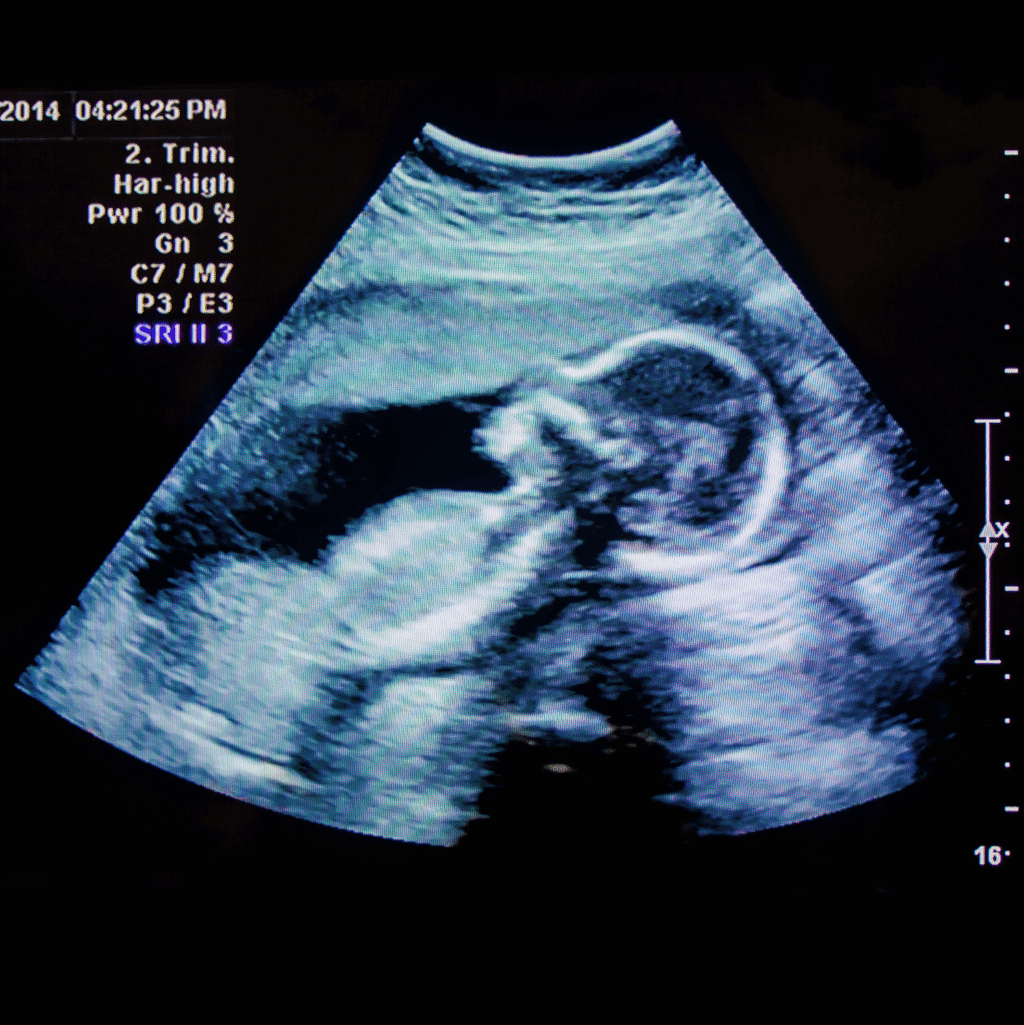

סקירת מערכות מאוחרת הינה בדיקת אולטרה-סאונד המבוצעת בשבועות 20-24 להריון.

הבדיקה מכונה גם "סקירת מערכות של הטרימסטר או השליש השני" והיא דומה באופייה לסקירת המערכות המוקדמת. משמע, מדובר בבדיקת אולטרה-סאונד, בלתי פולשנית וללא קרינה מייננת